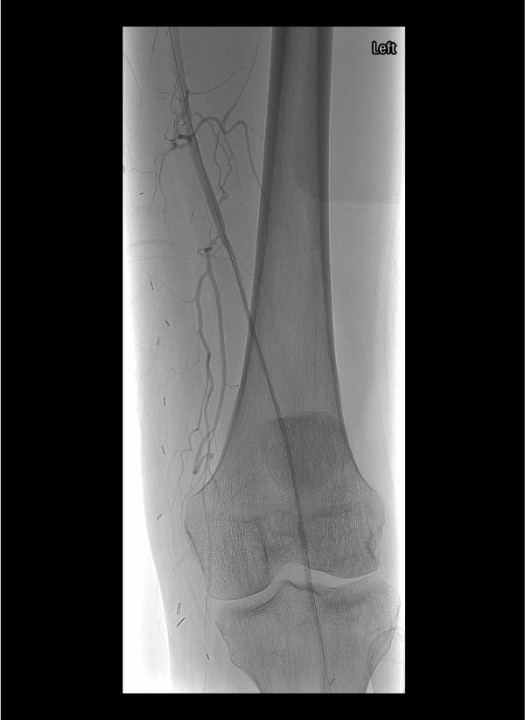

Angiographic Assessment & Endpoints

- Runoff angiography through sheath: 4 mL/s × 8 mL for outflow vessels; increase to 16–20 mL for lower leg and foot imaging

- Document baseline outflow to foot before initiating any intervention

- After crossing occlusion, gentle test injection to confirm intraluminal position and distal flow

- Select infusion catheter (Unifuse) to span entire lesion length; available in 10 cm increments (10–50 cm)

- Angiographic endpoints: restoration of inline flow, resolution of filling defects, treatment of underlying lesion

- If >50 cm occlusion, position 50 cm catheter with proximal marker at proximal extent; lytic medication flows distally as flow re-establishes